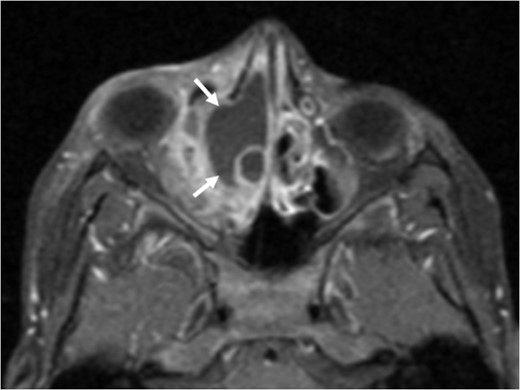

Axial T1 post-contrast sequence with fat suppression demonstrating peripheral enhancement (white arrows) but no internal or solid enhancing components to suggest that this is a secondary ABC.